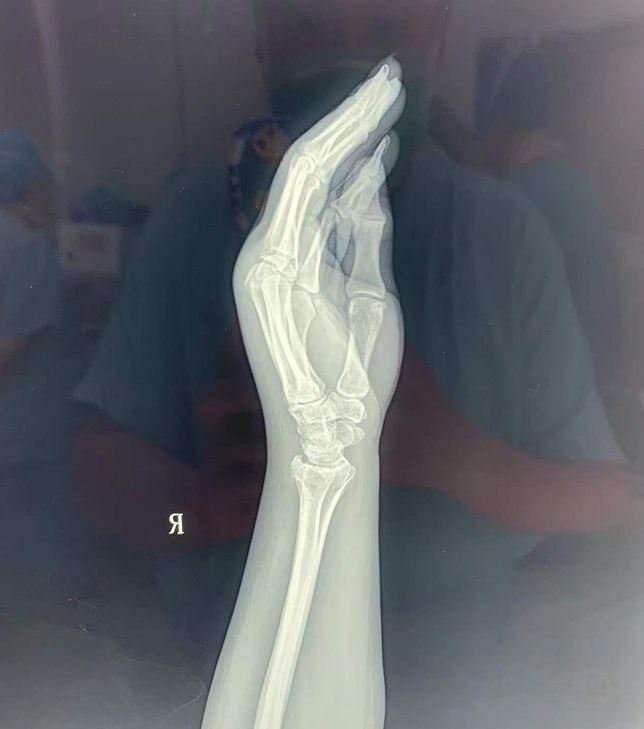

1// 腕架

本病例由中国中医科学院望京医院骨综科提供(术者:支架医生常医师)

【基本资料】患者,女,61岁

本病例腕架骨折。术前正侧位片:右桡骨远端骨折。

采用常规方法固定,自掌骨尺侧,约基底稍偏远处穿入螺纹针。

外架马蹄环穿过骨针,更方便调整固定角度。